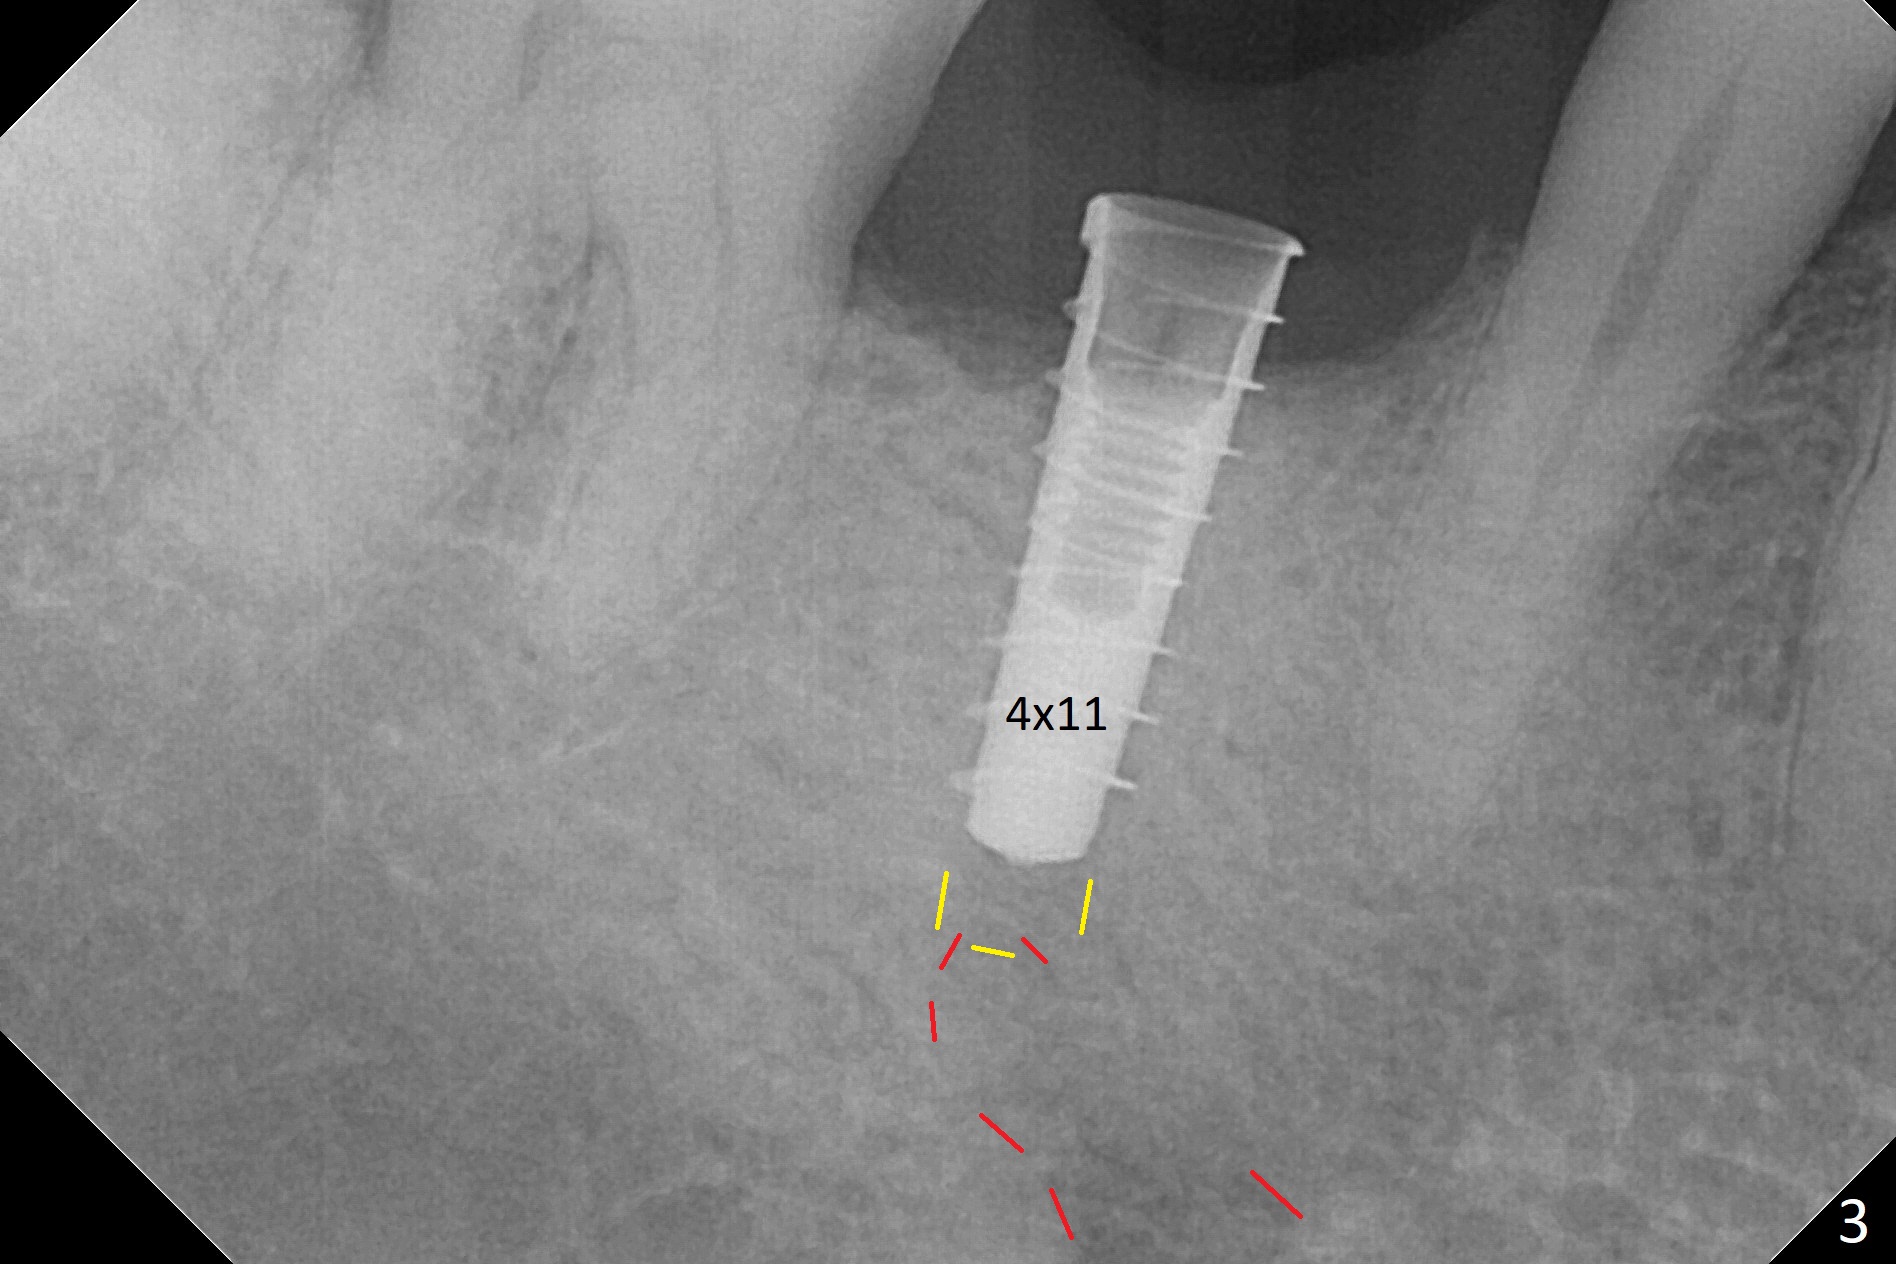

The retained deciduous tooth (lower right 2nd molar, Fig.1 T) has buccal apical infection and recession. After extraction, the initial depth of osteotomy is 11 mm over the flat socket bottom (Fig.2) without visible Mental Loop. Following 3.8 mm Magic Drill for 11 mm, a 4x11 mm dummy implant is placed partially due to hard bone; it appears that the apical osteotomy (Fig.3 yellow outline) overlaps the Mental Loop (red dashed line). For safety, a 4x9 mm IBS implant is placed with insertion torque 40 Ncm; a 5x5.7(4) mm abutment is immediately placed for an immediate provisional to cover the large socket and keep Vera graft in place (Fig.4 *). There is no postop paresthesia, probably due to the fact that the osteotomy is lingual to the Mental Loop. The provisional remains in place 7 days postop; its margin (Fig.5 arrow) covers the socket. The margin of the provisional is trimmed 1 month postop. Impression is taken nearly 3 months postop (Fig.6). The buccal plate looks atrophic 3 months postop (Fig.7 (immediately before cementation)), although there is no sign of periimplantitis. In the future, insert the immediate provisional inside of the buccal gingiva to make the buccal gingiva look bulky instead of buccal to it (Fig.5). The second drawback of placing an implant at the deciduous tooth area is that the crown is wide mesiodistally if orthodontic treatment is not rendered. Although there is lower anterior crowding, the patient declines orthodontic treatment. The bone density around the implant increases 7 months post cementation (Fig.8 *). The higher density bone seems to extend coronally 1 year 7 months post cementation (Fig.9). The dense bone apparently extends toward the abutment as well 3 years 5 months post cementation (Fig.10 curved arrows).